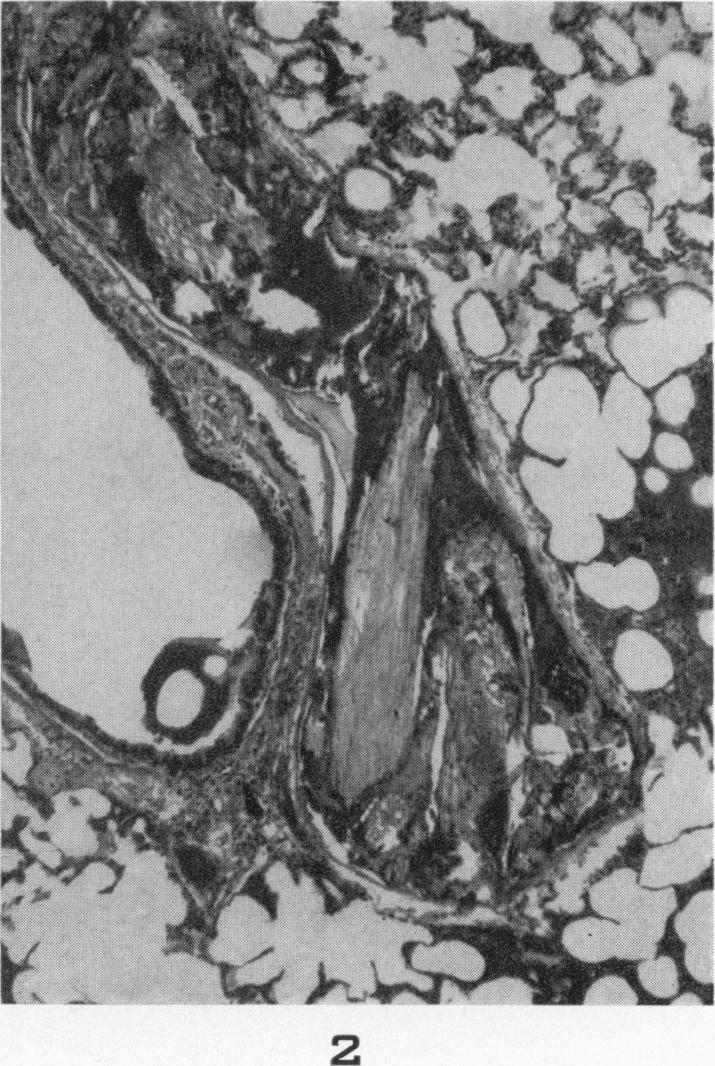

Chyme emboli in the lungs of goats wounded by missiles.

Am J Pathol. 1956 Jul-Aug;32(4):831-43.